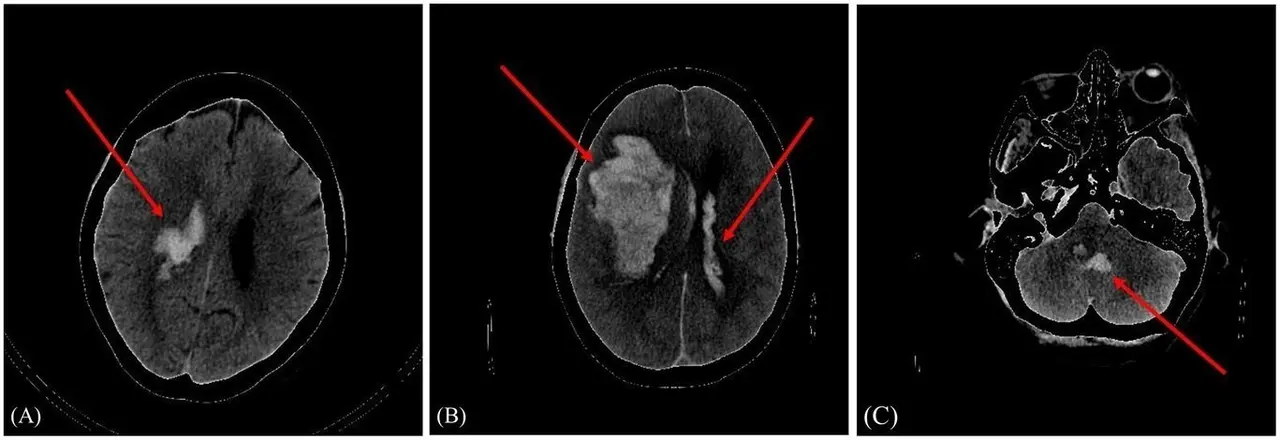

"Incluimos en el estudio a 262 pacientes de Cantabria que llegaban al servicio de urgencias de Valdecilla con sospechas de hemorragia intracraneal y con las imágenes de los distintos TAC cerebrales y sus datos clínicos, entrenamos un modelo personalizado para poder clasificar a los pacientes en mal pronóstico y buen pronóstico, utilizando un modelo híbrido", ha explicado Amaia Pérez.

El modelo se conoce como híbrido porque incluye dos grupos de datos: las imágenes del TAC y datos de cada paciente, y, por tanto, el rendimiento de la red mejora, "a más datos, mejores predicciones". Esos datos se obtienen de información personal, como la edad, sexo, si el paciente es fumador o consumidor de alcohol habitual o si tiene antecedentes médicos, entre otros.